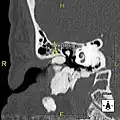

-

Normal ear canal -

Exostosis in ear canal -

Exostosis in ear canal